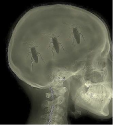

Навеяло:d

Вложения: